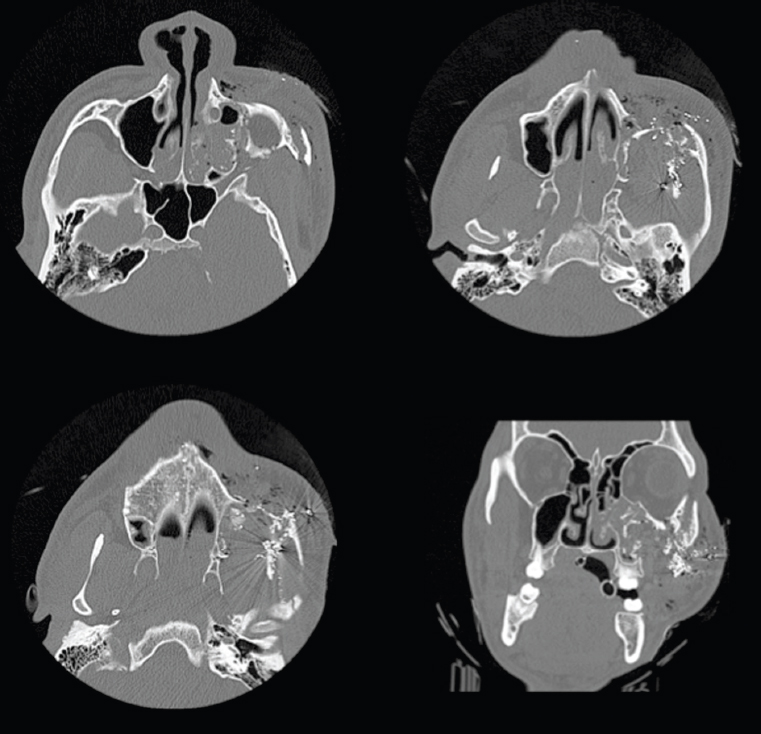

The zygoma is a spatially complex bone that articulates with the frontal bone, maxilla, temporal bone, and sphenoid. Zygomaticomaxillary complex (ZMC) fractures that occur with lower-velocity blunt impact often occur at these articulations. Spatially, they displace the ZMC with minimal comminution (Figure 15.2). Higher-velocity injuries (e.g., gunshot wounds) often cause comminution with more complex fracture patterns (Figure 15.3). By definition, given the anatomy of the zygoma, a ZMC fracture must affect the orbital floor or lateral orbital wall. Simultaneous reconstruction of the orbital floor is often indicated. ZMC fractures may cause deformity in facial width, orbital rim step-offs, cheek projection, and globe position. Medial displacement of the temporal process may cause trismus through impingement on the coronoid.